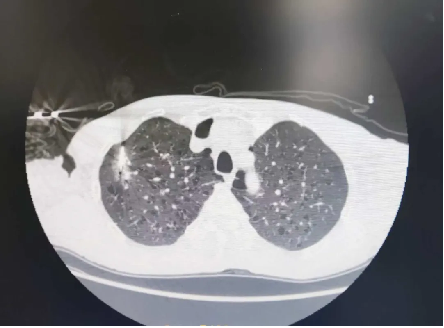

其次,精准医疗在呼吸科疾病诊断中也发挥着重要作用。借助先进的影像学技术和人工智能算法,医生能够更精准地识别肺部疾病的类型和分期。例如,在肺癌的诊断中,通过CT或彩超引导下的穿刺活检,结合病理学和分子分型技术,医生可以明确肿瘤的基因变异情况,为制定精准的治疗方案提供依据。

此外,呼吸介入治疗作为精准医疗的重要组成部分,在呼吸科的应用日益广泛。例如,对于晚期肺癌患者,呼吸科医生可通过气管镜、经皮穿刺介入治疗等方法,进行气道内病灶祛除、支架置入、球囊扩张、局部消融及冷冻等治疗,以缓解呼吸道症状,提高患者的生活质量。这些介入治疗技术不仅创伤小、恢复快,而且能够精准定位病灶,实现个性化治疗。